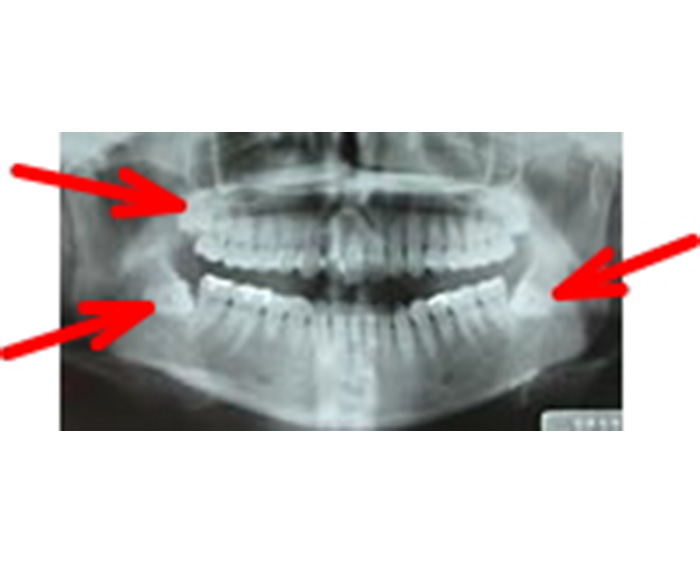

智歯(おやしらず)は18歳頃から萌出を開始しますが、現代の日本人の顎の大きさは小さくなっている傾向にあります。第3大臼歯である智歯はスペースがないため顎骨に埋伏している状態(埋伏智歯または水平埋伏智歯)の患者様が多く見られます。

このような顎骨に埋伏した智歯が原因となり歯肉の腫れ、痛みを繰り返し起こすことがあります。

当科では、術前に歯科用3次元CTを用いて正確な診断を行い、炎症がある場合は抗生剤を用いて消炎後、抜歯を行っています。埋伏智歯の場合、歯肉粘膜の切開、骨の削除、智歯の分割、創部の縫合を必要とします。

埋伏状智歯患者のオルソパントモ写真

左側下顎水平埋伏智歯

右側下顎水平埋伏智歯